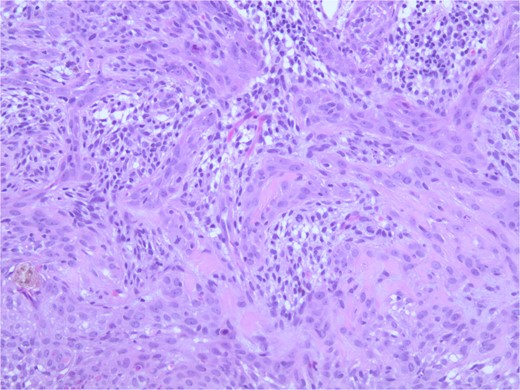

At the time of the surgery, the lesion was excised with 5 mm margins, given the acceptable margins of 4 mm for nonmelanoma skin cancer [4]. Macroscopic examination of the lesion revealed a well-defined, hyperpigmented, macular lesion with pathology positive for infiltrating BSC with negative margins confirmed on histology. Histology was notable for predominantly basal cell morphology with areas of squamous differentiation. The presence of the basal cell carcinoma component is demonstrated (Fig. 1). The BSC with abnormal squamous keratinization is also demonstrated (Figs 2–4). These studies were conducted on routine hematoxylin and eosin stains confirming the diagnosis of BSC. The patient was seen in the office, and at 2 months postoperative, there were no clinical concerns.

Microphotograph revealing BSC with abnormal squamous keratinization on histology.